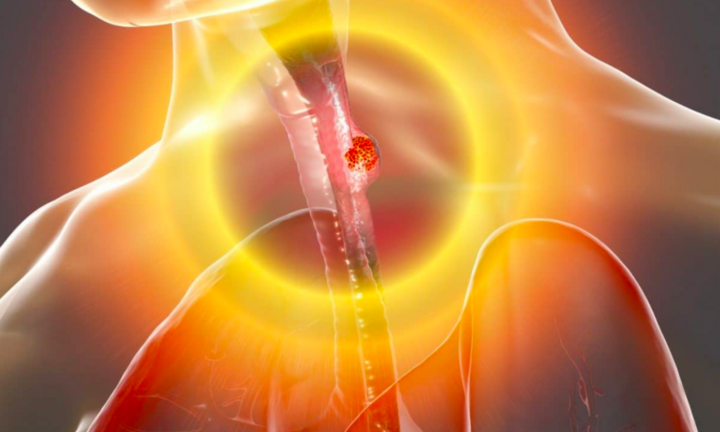

4 thói quen ‘nuôi lớn’ ung thư thực quản: Cách ăn uống sai gây hậu quả lớn nhất

Theo các bác sĩ trên kênh Family Doctor, ung thư thực quản có liên quan đến chế độ ăn uống, để tránh xa căn bệnh quái ác này, hãy sớm tránh 4 thói quen dưới đây.

Theo các bác sĩ trên kênh Family Doctor, ung thư thực quản có liên quan đến chế độ ăn uống, để tránh xa căn bệnh quái ác này, hãy sớm tránh 4 thói quen dưới đây.